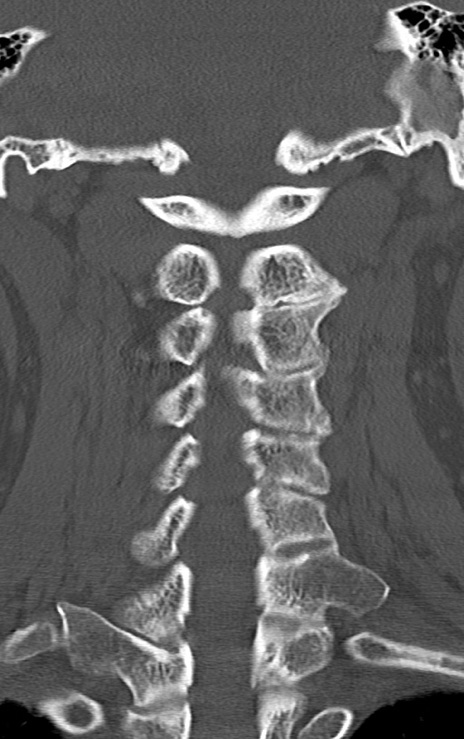

頚椎CT

矢状断像